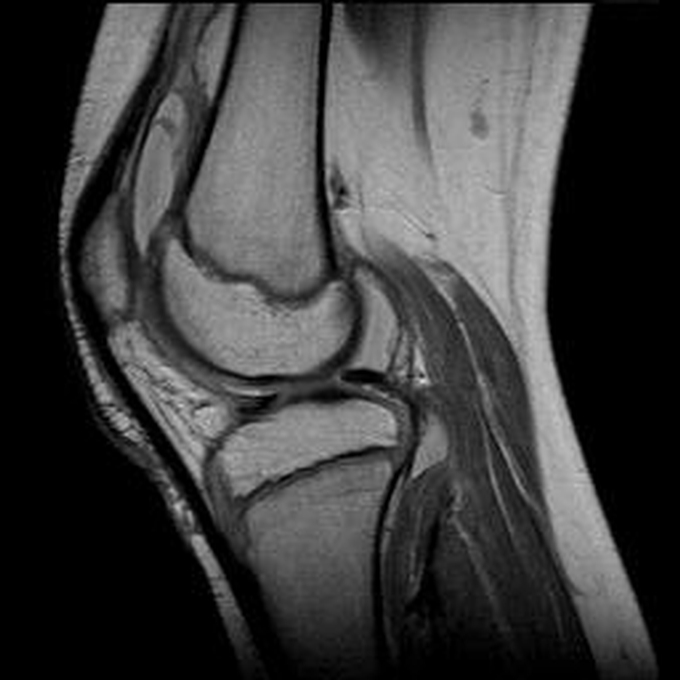

Haemophiliearthropathie bei Haemophilie A.

ARC123 Haemophiliearthropathie bei Haemophilie A.

MRT (high)